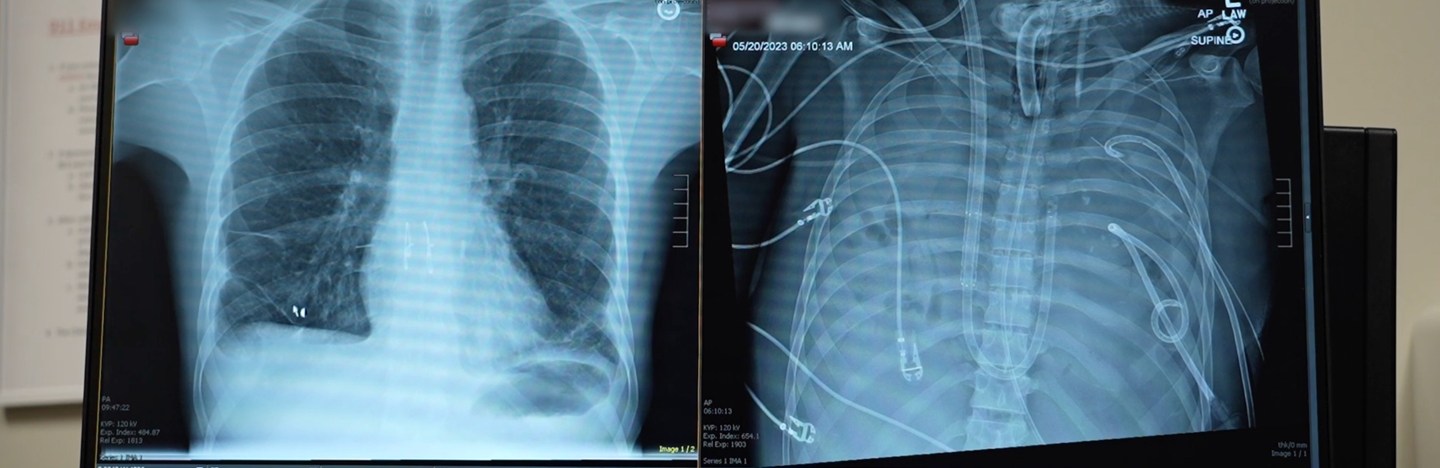

Artificial lungs kept a man alive until he could get a transplant

A new artificial lung system might keep people without lungs alive for weeks. Like real lungs, tubes and pumps oxygenate blood and maintain blood flow.